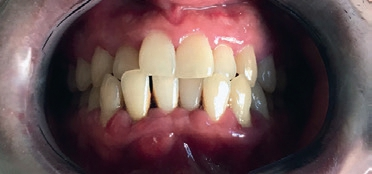

Zur Verdeutlichung sollen die neuen Kriterien abschließend auf einen konkreten klinischen Fall angewendet werden (Abb. 1–3). Es handelt sich um einen 25-jährigen Patienten, der sich auf Überweisung des Hauszahnarztes vorstellt und über zunehmende Schmerzen beim Abbeißen und eine seit Tagen bestehende und größer werdende Gingivaschwellung im Frontzahnbereich des Unterkiefers berichtet. Die allgemeinmedizinische Anamnese ist unauffällig, der Patient ist Nichtraucher. Intraoral zeigt sich eine druckdolente Schwellung vestibulär in regio 41/42, massive Zahnsteinablagerungen lingual an den unteren Frontzähnen und vestibulär der oberen Molaren, Entleerung von Pus aus den Sulci der Zähne 31 – 43. Einzelne Zähne weisen eine pathologische Mobilität auf (42/Grad III, 41/II, 31/I, 32/I) bei positivem Befund der thermischen Vitalitätsprüfung.

Prof. Dr. Peter Hahner, Prof. Dr. Georg Gaßmann

Aus den klinischen und röntgenologischen Befunden können als Diagnosen formuliert werden:

- parodontaler Abszess in regio 42 und 41 als Folge einer bisher unbehandelten Parodontitis

- Parodontitis (Stadium III, generalisiert; Grad C – schnelle Progression)

Das Staging folgt aus den klinischen und röntgenologischen Parametern, da mehrere Zähne Sondierungstiefen über 6 mm und einen vertikalen Knochenabbau aufweisen (Abb. 2 und 3; vgl. Tab. 2). Zum Grading existiert zwar keine direkte Evidenz für einen Attachmentverlust von mehr als 2 mm in den vergangenen 5 Jahren, da keine Befunde aus der Vergangenheit vorliegen. Der Quotient aus prozentualem Knochenverlust und Alter erreicht aber an mehreren Zähnen einen Wert von über 1,0. Trotz der hohen Menge an vorhandenem Biofilm übersteigt die schon stattgefundene parodontale Destruktion erheblich das für einen 25-jährigen Patienten erwartbare Ausmaß. Der Patient stellt sich zudem in einem Stadium rascher Krankheitsprogression vor (vgl. Tab. 3).

Auf der Grundlage dieser Diagnosen können die Behandlungsplanung und die prognostische Einschätzung erfolgen. Der parodontale Abszess erfordert eine Akutbehandlung vor Beginn der systematischen Parodontitistherapie. Eine Erkrankung im Stadium III (schwere Parodontitis) bedingt über die mechanische antiinfektiöse Therapie hinaus komplexe, ggf. chirurgische parodontologische Interventionen. Die vermutete schnelle Progression (Grad C) gibt Hinweise auf mögliche Probleme während der Therapie und auf ein erhöhtes Risiko für Rezidive und weiteren Attachmentverlust in der Zukunft. Diese Faktoren müssen in der Patientenberatung und individualisierten Therapie zur Auswahl der Therapieoptionen mit der höchsten Evidenz für einen Behandlungserfolg und für die Organisation der Erhaltungstherapie berücksichtigt werden.